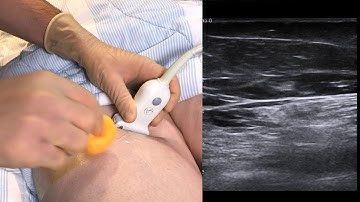

How To: Ultrasound Guided Saphenous Nerve Block 3D Video